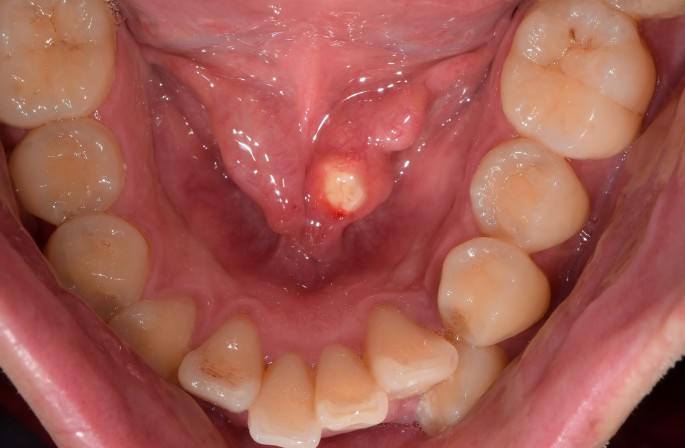

1) 한 손은 입속에서, 다른 한 손은 목 밖에서, 손가락을 이용해 침샘과 침샘관 부위를 만져보고 진단합니다.

2) 경부 CT, 구강저 단순촬영 : 침샘들을 중심으로 목 부위의 CT 촬영을 해서 타석증을 확인합니다.

3) 타액선관 조영술 : 타액선관에 가느다란 관을 넣어 조영제를 주입해 타액선관의 상태, 타석의 유무, 위치 등을 검사합니다.

4) 초음파 검사 : 초음파는 타석을 투과하지 못하는 성질이 있으므로 침샘이나 침샘관 주위를 초음파로 관찰하면 타석을 진단할 수 있습니다.